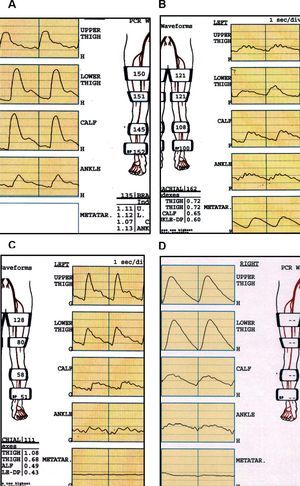

El registro de las ondas de volumen del pulso a lo largo de la extremidad mediante pletismografía es especialmente útil en pacientes en los que la calcificación arterial impide un registro fiable de las presiones sistólicas. El registro transmetatarsiano o digital aporta una importante información sobre el estado de la vascularización en esta zona, que difícilmente puede conseguirse con otros métodos (fig. 1).

Fig. 1. Estudio de presiones segmentarias y onda de volumen según el sector afectado. A: estudio normal: ondas volumen de pulso (PVR) con onda dícrota. Índices segmentarios > 1 en todas las localizaciones. B: oclusión iliaca: aplanamiento de PVR e índices < 1 desde muslo proximal. C: oclusión femoropoplítea: PVR e índices en muslo proximal normales. Aplanamiento distal de PVR con índice < 1 en tobillo. D: calcificación intensa: no se colapsan los vasos pese a que las presiones en el manguito son muy altas (índice tobillo-brazo falsamente elevado). PVR muy patológicos, planos en los transmetatarsianos.